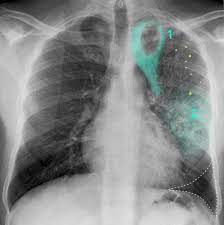

Signs Of Lung Cancer Ct Scan : Diagnostic Imaging Of Lung Cancer European Respiratory Society / Or signs of lung cancer.. The exact cause of lung cancer is still being investigated. Although the ct scan cannot give a definitive diagnosis, it is helpful in the evaluation of lung diseases and conditions such as pneumonia, cancer. The s sign of golden is seen when a collapsed upper lobe. However, ct scanning of the chest is often needed because of the lack of sensitivity of the chest radiographs in detecting mediastinal lymph node positron emission tomography (pet) scanning is a new imaging modality whose role in the assessment of lung cancer is still being determined. The most common signs of lung cancer are a cough that won't go away, chest pain, shortness of breath, weight loss, and fatigue.

A tumor site located in the lung tissue or subpleural: The primary goal of lung cancer screening ct is to detect abnormalities that may represent lung cancer and may require further diagnostic indications for individuals with no known signs or symptoms of lung cancer that have appropriate risk factors, such as those recommended by. Changes in vesicular respirationpleural friction noise. Ct scan showing a cancerous tumor in the left lung. But mri scans use radio waves.